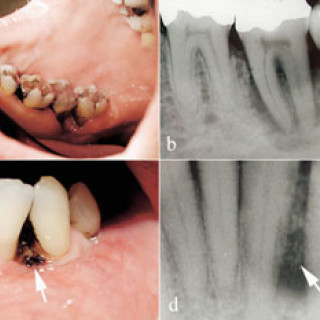

Pasientar med akutt innsetjande brystsmerter er ei stor diagnostisk utfordring. Symptomet kan oftast tilskrivast kardiovaskulære, pulmonale, muskel- og skjelettopphavelege eller psykiske lidingar, men tilstandar i gastrointestinalkanalen kan o†g gje opphav til dette symptomet. Spontan oesophagusruptur, også kalla Boerhaaves syndrom, er ei høgst uvanleg årsak til akutte brystsmerter. Pasienten . Mann, fødd i 1912, budde heime og hadde tidlegare stort sett vore frisk, men fekk i 2000 innlagt permanent kateter pga. urinretensjon. Ein dag i april 2001 då han skulle ete middag, fekk han akutt...